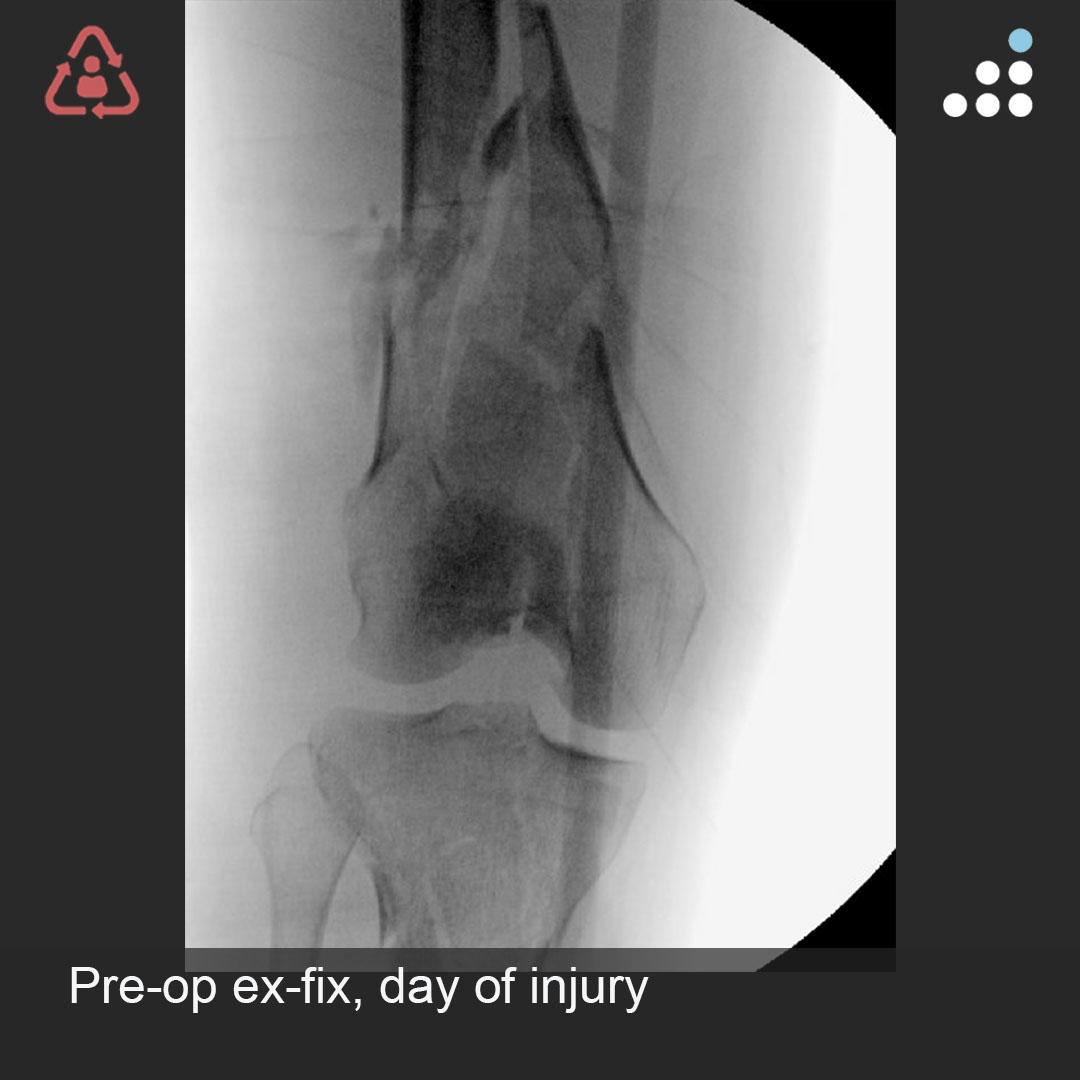

Orthobullets on Twitter "Here are intraop & postop images of yesterday's case by Dr. Michael Floating Knee Injury Orthobullets Floating knee is a flail knee joint resulting from fractures of the shafts or adjacent metaphyses of the femur and ipsilateral tibia (see image below). Floating knee injuries may include a. Ipsilateral fractures of the femur and tibia have been called floating knee injuries and may include combinations of diaphyseal,. The traumatic floating knee in adults (fk) is a combined. Floating Knee Injury Orthobullets.